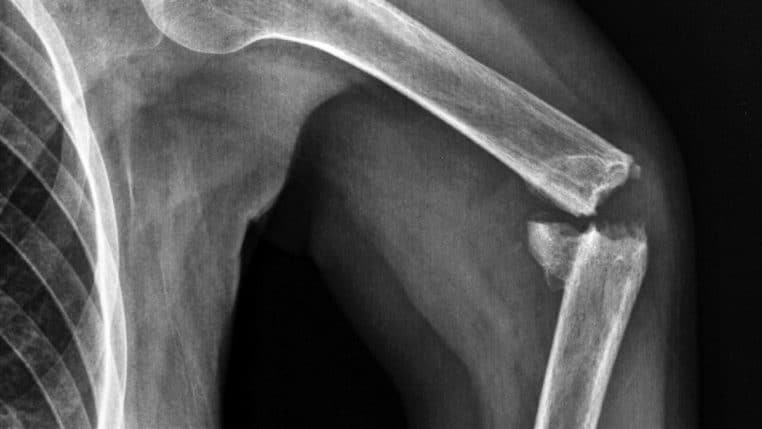

Les différences lorsqu’un adulte et un enfant se cassent les os et… des théories farfelues

Bien que moins visibles que les rides, les os sont de parfaits indicateurs de l’âge. En effet, ces constituants de votre corps vieillissent en même temps, sinon plus vite que vous. De plus, ils guérissent plus difficilement chez les adultes. Cela peut être dû à l’âge, mais aussi à plusieurs autres facteurs indépendants de votre volonté. Les enfants ont décidément une vie dorée !

Combien de fois avez-vous ou entendu un parent interdire à son enfant de courir sous peine de se casser un os ? Pourtant, ces petits turbulents ne sont pas ceux qui risquent de souffrir le plus si cela devait arriver. En effet, les adultes auront le plus de mal à se remettre sur pied s’ils devaient subir une fracture !

Ces experts estiment que les os des adultes prennent des mois à guérir, tandis que ceux des enfants ne nécessitent que quelques semaines. Selon ces spécialistes : « Contrairement aux os du corps adulte, les os des enfants sont encore en croissance, leur modèle de croissance peut donc plus facilement s’adapter aux os cassés ou fracturés ».

Les représentants de Total Orthopaedic Care attribuent cette magnifique capacité des enfants au périoste. Il s’agit de tissu conjonctif qui recouvre l’ensemble du squelette et qui se retrouve en grande quantité chez les enfants. Cette sorte d’armure : « rend leurs os plus épais et plus solides ».

Certes, les grandes personnes en possèdent, mais en quantité moindre par rapport à leur progéniture. De plus, la présence massive de périoste « signifie également que le temps de récupération et de guérison est beaucoup plus rapide ».

En fait : « les os sont beaucoup plus riches en oxygène, ce qui leur permet de guérir plus facilement après un traumatisme ». Néanmoins, la richesse en périoste peut jouer des tours aux enfants. Les fractures minimes deviennent plus difficiles à détecter. Voilà pourquoi les parents doivent redoubler de vigilance et rester à l’écoute après une chute !

Il ajoute que les caractéristiques de cet élément sont « en grande partie héréditaire ». Néanmoins, il ne faut pas négliger les gènes récessifs. Par ailleurs, les adultes souffrent plus généralement de « fractures dues à l’usure ». De leur côté, les enfants sont plus souvent victimes de « traumatismes ou blessures sportives ».

Sachez que « le cartilage et les os se dégradent au fil du temps, comme cela peut se produire en cas d’arthrite ou d’ostéoporose, ce qui entraîne une fracture plus facile des os en cas de chute ». La prudence s’impose donc pour les seniors !